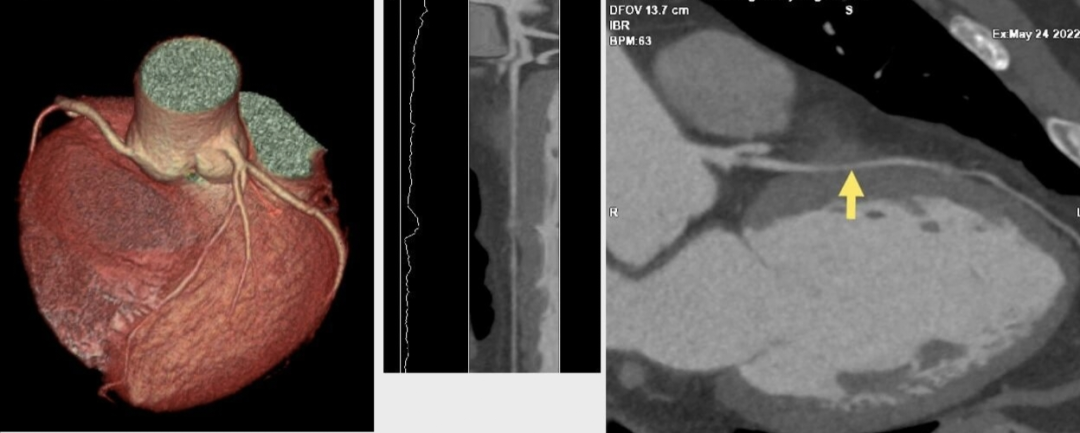

直到他接受我院双源CT冠状动脉CTA检查,真相才水落石出。图像清晰显示,他的左前降支中段(一支关键的心脏供血动脉)有一段走行于心肌纤维之下。在心脏舒张期,这段血管看似正常;但在心脏收缩期,这段血管被上方的心肌明显挤压、变窄——典型的“心肌桥”。

正是这个藏在心肌里的“桥”,在运动时随着心跳加剧而强力收缩,压迫冠状动脉,导致心肌暂时性缺血,引发胸闷胸痛。明确诊断后,医生为他制定了针对性的药物治疗和运动方案,症状得到有效控制,避免了病情的进一步发展与误判。

(↑ 冠状动脉CTA影像)